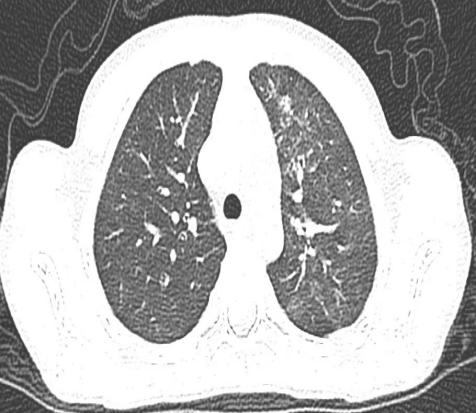

儿科二区近期收治了1名 7 岁的患儿,因 “反复发热伴咳嗽 4 天” 前往申冬冬副主任医师门诊就诊。初步完善胸部彩超后,提示患儿存在肺实变,病情较重,遂紧急收治入院。入院后,乔淑楠主治医师结合患儿症状、体征及彩超结果,判断肺部感染情况复杂,建议进一步完善胸部 CT 及呼吸道病原学检查。检查结果证实:患儿左肺上叶炎症伴部分实变,且存在肺炎支原体阳性,凝血功能异常;更危险的是,患儿左上肺出现大面积肺不张。

经过全科医护人员的精心治疗与护理,患儿病情逐步好转,复查胸部 CT 显示左肺上叶炎症明显吸收,肺不张情况得到显著改善,目前已顺利康复出院,赢得了家属的高度赞誉。